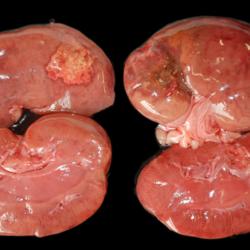

Pàgina anterior de 637 Pàgina següent 3181 total Canine Specie: Canine Organ: Kidney Lesion: Infarction Lesion modifier: - Disease: - Files/Expedient: N-201/15 Position: 252 (1 views) Canine Specie: Canine Organ: Heart Lesion: Endocarditis Lesion modifier: Endocarditis - Valvular Disease: - Files/Expedient: N-201/15 Position: 252 (1 views) Canine Specie: Canine Organ: Heart Lesion: Hemorrhage Lesion modifier: - Disease: Infectious canine hepatitis Files/Expedient: N-583/09 Position: 136 (2 views) Canine Specie: Canine Organ: Liver Lesion: Hepatitis Lesion modifier: Hepatitis - Necrotizing Disease: Infectious canine hepatitis Files/Expedient: N-583/09 Not viewed Canine Specie: Canine Organ: Stomach Lesion: Gastritis Lesion modifier: Gastritis - Hemorrhagic Disease: Infectious canine hepatitis Files/Expedient: N-373/12 Not viewed Pàgina anterior de 637 Pàgina següent Títol Select...Avian (Exotic) (110)Avian (Poultry) (76)Bovine (317)Canine (935)Caprine (47)Equine (257)Feline (326)Ferret (19)General (127)Marine mammal (22)Non-human primate (20)Ovine (328)Porcine (379)Rabbit (61)Reptile (38)Rodent (28)Wildlife (91) Format Select...- (60)Abomasum (37)Adrenal gland (10)Blood (7)Blood vessel (50)Body as a whole (19)Bone (57)Bone marrow (21)Brain (93)Cloaca (1)Diaphragm (2)Ear (5)Esophagus (39)Eye (16)Fetus (12)Gallbladder (23)Gizzard (2)Heart (265)Intestine (356)Joint (32)Kidney (443)Larynx (5)Liver (326)Lung (264)Lymph node (91)Mammary gland (10)Mediastinum (1)Muscle (22)Nasal cavity (22)Nerve (7)Omasum (5)Oral cavity (63)Ovary (14)Oviduct (8)Pancreas (7)Parathyroid (5)Penis (10)Peritoneum (65)Pharynx (9)Pituitary gland (6)Placenta (7)Prostate (8)Proventriculus (3)Reticulum (1)Rumen (28)Sinus (7)Skin (181)Spinal cord (15)Spleen (105)Stomach (125)Teeth (1)Testicle (11)Thoracic cavity (31)Thymus (13)Thyroid gland (5)Tongue (32)Tonsils (11)Trachea (11)Urethra (5)Urinay bladder (61)Uterus (27)Vagina (1)Vulva (1)Yolk sac (1) Cobertura Select...- (152)Abomasitis (26)Abscess (27)Acidosis (1)Adenocarcinoma (20)Adenoma (9)Aerosacculitis (6)Agenesis (1)Agnathia (1)Alopecia (7)Amyloidosis (12)Aneurysm (6)Angiectasis (1)Anthracosis (1)Arteritis (11)Arthritis (15)Arthrogryposis (6)Artifact (4)Ascites (13)Atelectasis (8)Atherosclerosis (5)Atresia (1)Atrial septal defect (2)Atrophy (10)Autolysis (7)Bronchitis (6)Bronchopneumonia (26)Cachexia (2)Carcinoma (103)Cardiomyopathy (19)Cellulitis (2)Chemodectoma (4)Cholangiohepatitis (4)Cholangitis (19)Cholecystitis (4)Cholestasis (5)Chondrodysplasia (2)Chondrosarcoma (2)Chronic passive congestion (13)Chylothorax (2)Cirrhosis (6)Coelomitis (3)Coenurus cerebralis (4)Colitis (40)Congestion (17)Conjunctivitis (5)Coronitis (3)Cryptorchidism (3)Cyst (25)Cystitis (24)Dermatitis (69)Diaphragmatic hernia (4)Dilation (28)Discospondylitis (1)Disseminated intravascular coagulation (7)Dyschondroplasia (1)Dysplasia (29)Ectopia cordis (1)Ectopic ureter (1)Edema (55)Emphysema (5)Encephalitis (5)Endocardiosis (14)Endocarditis (26)Endometritis (5)Enteritis (118)Enterolith (6)Epulis (3)Esophagitis (14)Fasciitis (1)Fibrosis (7)Fibrous osteodystrophy (8)Fistula (1)Folliculitis (3)Fracture (2)Gastritis (34)Gingivitis (5)Glioma (8)Glomerulonephritis (21)Glossitis (25)Glycogenosis (1)Gout (8)Granuloma (2)Granulosa cell tumor (4)Hemangioma (9)Hemangiosarcoma (46)Hematoma (8)Hemoglobinuria (2)Hemopericardium (12)Hemoperitoneum (2)Hemorrhage (100)Hemosiderosis (7)Hemothorax (2)Hepatitis (78)Hernia (11)Histiocytosis (3)Hydatid cyst (11)Hydrocephalus (9)Hydrometra (1)Hydronephrosis (22)Hydropericardium (6)Hydrothorax (3)Hydroureter (5)Hyperkeratosis (8)Hyperostosis (4)Hyperplasia (37)Hypertrophy (9)Hypopigmentation (1)Hypoplasia (7)Hypopyon (1)Impaction (6)Infarction (63)Insulinoma (6)Intussusception (5)Jaundice (17)Laminitis (2)Laryngitis (2)Leiomyoma (5)Leukemia (13)Lipidosis (36)Lipoma (7)Lymphadenitis (45)Lymphadenopathy (7)Lymphangiectasia (6)Lymphangitis (5)Lymphoma (221)Malacia (11)Malignant melanoma (15)Mast cell tumor (11)Mastitis (8)Megaesophagus (2)Melanosis (3)Melena (4)Meningioma (6)Meningitis (6)Meningocele (2)Meningoencephalitis (5)Mesothelioma (5)Methemoglobinemia (2)Mineralization (10)Mucocele (5)Mucometra (1)Multilobular bone tumor (1)Mummification (3)Myelofibrosis (1)Myocarditis (4)Myositis (5)Necrosis (81)Nephritis (113)Nephroblastoma (6)Nephrosclerosis (1)Nephrosis (14)Neuritis (1)Obstruction (13)Omasitis (4)Omphalitis (1)Omphalophlebitis (7)Orchitis (4)Osteoarthrosis (5)Osteomyelitis (9)Otitis (2)Palatoschisis (3)Pancreatitis (3)Panniculitis (3)Papilloma (7)Parakeratosis (14)Patent ductus arteriosus (6)Peliosis hepatis (1)Perforation (17)Pericarditis (35)Peritonitis (39)Persistent right aortic arch (1)Pharyngitis (2)Pheochromocytoma (2)Phlebitis (2)Placentitis (6)Pleuritis (21)Pleuropneumonia (24)Pneumonia (109)Pneumothorax (3)Polycystosis (14)Polyp (5)Polyserositis (6)Posthitis (1)Proctitis (4)Prolapse (3)Prostatitis (3)Proventriculitis (1)Pyelonephritis (24)Pyometra (6)Pyothorax (4)Rhinitis (11)Rumenitis (6)Rupture (24)Salpingitis (3)Sarcoma (57)Sclerosis (1)Scoliosis (2)Seminoma (2)Sequestrum (2)Serous atrophy (14)Sinusitis (7)Splenitis (14)Splenomegaly (9)Spondylitis (6)Spondylosis (1)Stenosis (9)Stomatitis (32)Tenosynovitis (2)Teratoma (3)Thricobezoar (2)Thrombosis (16)Tonsilitis (4)Torsion (13)Tracheitis (4)Tympany (7)Typhlitis (8)Typhlocolitis (4)Ulcer (43)Urethritis (1)Urolithiasis (36)Uroperitoneum (1)Uveitis (1)Vasculitis (15)Ventricular septal defect (3)Volvulus (11) Matèria Select... - (14)- (1653)- (152)Abomasitis - Catarrhal (2)Abomasitis - Catarrhal-hemorrhagic (1)Abomasitis - Chronic (1)Abomasitis - Fibrinous-necrotizing (2)Abomasitis - Hyperplasic (5)Abomasitis - Hyperplasic - Chronic (1)Abomasitis - Necrotic (1)Abomasitis - Necrotizing (2)Abomasitis - Ulcerative (5)Adenocarcinoma (9)Aerosacculitis - Granulomatous (1)Amyloidosis - Chronic (1)Arteritis - Necrotic (2)Arteritis - Necrotizing (1)Arthritis - Chronic (4)Arthritis - Fibrinous-purulent (3)Arthritis - Serous (4)Arthritis - Subacute (1)Ascites - Serous (1)Atrophy - Serous (1)Bronchitis - Catarrhal (3)Bronchitis - Suppurative (1)Bronchopneumonia - Catarrhal-purulent (17)Bronchopneumonia - Fibrinous (1)Bronchopneumonia - Granulomatous (1)Bronchopneumonia - Purulent (1)Bronchopneumonia - Suppurative (5)Carcinoma - Adenocarcinoma (33)Carcinoma - Adenocarcinoma - Hepatocellular (2)Carcinoma - Adenocarcinoma - Mucinous (1)Carcinoma - Basosquamous (1)Carcinoma - Cholangiocellular (3)Carcinoma - Hepatocellular (4)Carcinoma - Metastatic (3)Carcinoma - Squamous cell carcinoma (13)Carcinoma - Transitional cell (2)Cardiomyopathy - Dilated (13)Cardiomyopathy - Hypertrophic (6)Cellulitis - Necrotizing (1)Cholangitis - Chronic (8)Cholangitis - Hyperplasic (3)Cholecystitis - Fibrinous-necrotizing (1)Coelomitis - Fibrinous (1)Coelomitis - Granulomatous (1)Colitis - Catarrhal (3)Colitis - Catarrhal-hemorrhagic (1)Colitis - Fibrinous (1)Colitis - Fibrinous-necrotizing (1)Colitis - Fibrinous-necrotizing (Diphtheritic) (6)Colitis - Granulomatous (2)Colitis - Hemorrhagic (4)Colitis - Hemorrhagic-necrotizing (3)Colitis - Necrotizing (2)Colitis - Ulcerative (6)Congestion - Chronic (2)Conjunctivitis - Hyperplasic (1)Conjunctivitis - Purulent (3)Coronitis - Ulcerative (1)Cystitis - Chronic (3)Cystitis - Fibrinous (1)Cystitis - Fibrinous-necrotizing (1)Cystitis - Follicular (1)Cystitis - Hemorrhagic (6)Cystitis - Hemorrhagic-ulcerative (1)Cystitis - Necrotizing (9)Cystitis - Perforated (1)Dermatitis - Granulomatous (14)Dermatitis - Hyperkeratotic (10)Dermatitis - Hyperplasic (proliferative) (1)Dermatitis - Hyperplastic (10)Dermatitis - Necrotizing (4)Dermatitis - Pustular (4)Dermatitis - Ulcerative (2)Dilation - Chronic (1)Discospondylitis - Necrotizing (1)Dysplasia - Follicular (5)Edema - Interstitial (6)Emphysema - Interstitial (1)Encephalitis - Granulomatous (1)Encephalitis - Nonsuppurative (1)Endocardiosis - Mitral (7)Endocardiosis - Mitral - Chronic (5)Endocarditis - Valvular (6)Endocarditis - Valvular - Mitral (7)Endocarditis - Valvular - Pulmonic (1)Endocarditis - Valvular - Subacute (1)Endocarditis - Valvular - Subaortic (5)Endocarditis - Valvular - Tricuspid (4)Endometritis - Purulent (3)Endometritis - Purulent-hemorrhagic (2)Enteritis - Catarrhal (23)Enteritis - Catarrhal - Acute (1)Enteritis - Catarrhal-hemorrhagic (5)Enteritis - Catarrhal-hemorrhagic - Acute (2)Enteritis - Fibrinous (16)Enteritis - Fibrinous - Acute (3)Enteritis - Fibrinous-necrotizing (7)Enteritis - Granulomatous (14)Enteritis - Granulomatous - Chronic (1)Enteritis - Granulomatous - Multifocal (1)Enteritis - Hemorrhagic (17)Enteritis - Hemorrhagic - Acute (1)Enteritis - Hemorrhagic-necrotizing (1)Enteritis - Hyperplasic (proliferative) (4)Enteritis - Necrotizing (4)Enteritis - Necrotizing - Acute (1)Enteritis - Necrotizing - Hemorrhagic (1)Enteritis - Necrotizing-ulcerative (2)Enteritis - Ulcerative (1)Enteritis - Ulcerative-hemorrhagic (1)Esophagitis - Erosive-ulcerative (6)Esophagitis - Necrotizing (4)Esophagitis - Ulcerative (1)Esophagitis - Ulcerative-necrotizing (1)Fasciitis - Fibrinous-purulent (1)Folliculitis - Purulent (2)Gastritis - Catarrhal (2)Gastritis - Chronic (1)Gastritis - Follicular (1)Gastritis - Hemorrhagic (2)Gastritis - Hemorrhagic-necrotizing (1)Gastritis - Hypertrophic (2)Gastritis - Inclusion bodies (1)Gastritis - Mineralization (1)Gastritis - Mycotic (1)Gastritis - Necrotizing (2)Gastritis - Ulcerative (6)Gastritis - Uremic (3)Gingivitis - Erosive (2)Gingivitis - Hyperplasic (proliferative) (1)Gingivitis - Necrotizing (1)Glomerulonephritis - Chronic (7)Glomerulonephritis - Membranoproliferative (3)Glomerulonephritis - Membranoproliferative - Chronic (1)Glomerulonephritis - Membranous (3)Glomerulonephritis - Membranous - Chronic (1)Glomerulonephritis - Proliferative (2)Glomerulonephritis - Subacute (1)Glossitis - Erosive (2)Glossitis - Granulomatous (6)Glossitis - Hyperplasic (1)Glossitis - Hyperplasic (proliferative) (2)Glossitis - Hyperplastic (1)Glossitis - Necrotizing (2)Glossitis - Necrotizing - Focal (1)Glossitis - Ulcerative (6)Glossitis - Ulcerative - Multifocal (1)Glossitis - Ulcerative - Subacute (1)Glycogenosis (1)Granuloma - Eosinophilic (1)Hemangiosarcoma - Metastatic (2)Hemorrhage - Acute (1)Hemorrhage - Subcapsular (3)Hepatitis - Abscess (9)Hepatitis - Acute (3)Hepatitis - Chronic (4)Hepatitis - Chronic interstitial (6)Hepatitis - Granulomatous (7)Hepatitis - Interstitial - Multifocal (1)Hepatitis - Interstitial - Subacute (1)Hepatitis - Necrotizing (17)Hepatitis - Necrotizing - Acute (2)Hepatitis - Necrotizing - Hemorrhagic (1)Hepatitis - Necrotizing - Subacute (1)Hepatitis - Pyogranulomatous (7)Hepatitis - Subacute (4)Hydronephrosis - Chronic (1)Hydropericardium - Chronic (1)Hyperplasia - Erythroid (1)Hyperplasia - Lymphoid (3)Hyperplasia - Myeloid (1)Hyperplasia - Nodular (8)Hypertrophy - Concentric (2)Hypertrophy - Eccentric (3)Infarction - Acute (17)Infarction - Acute - Multifocal (2)Infarction - Chronic (5)Infarction - Chronic - Multifocal (1)Infarction - Subacute (18)Infarction - Subacute - Focal (2)Laminitis - Chronic (2)Laryngitis - Necrotic (1)Laryngitis - Necrotizing (1)Leukemia - Lymphoid leukemia (2)Leukemia - Non-lymphoid leukemia (6)Lipidosis - Multifocal (1)Lipidosis - Panlobular (1)Lipidosis - Panlobular - Generalized (2)Lymphadenitis - Granulomatous (24)Lymphadenitis - Granulomatous - Chronic (3)Lymphadenitis - Hemorrhagic (1)Lymphadenitis - Necrotizing (5)Lymphadenitis - Necrotizing (caseous) (11)Lymphangitis - Granulomatous (1)Lymphangitis - Purulent (1)Lymphangitis - Ulcerative (1)Lymphoma - Alimentary lymphoma (7)Lymphoma - Cutaneous lymphoma (6)Lymphoma - Lymphosarcoma (2)Lymphoma - Mediastinal lymphoma (1)Lymphoma - Multicentric lymphoma (29)Malignant melanoma - Malignant (1)Malignant melanoma - Metastatic (1)Mast cell tumor - Metastatic (1)Mastitis - Fibrinous-purulent (2)Mastitis - Necrotic (1)Mastitis - Purulent (3)Mastitis - Suppurative (1)Meningitis - Fibrinous-purulent (2)Meningitis - Purulent (4)Meningoencephalitis - Necrotizing (3)Meningoencephalitis - Nonsuppurative (2)Mineralization - Metastatic (4)Myocarditis - Fibrous - Chronic (1)Myocarditis - Granulomatous (1)Myositis - Purulent (2)Necrosis - Acute (1)Necrosis - Cortical (5)Necrosis - Follicular (1)Necrosis - Papillary (8)Necrosis - Papillary - Acute (3)Necrosis - Subacute (3)Necrosis - Tubular (6)Nephritis - Embolic (2)Nephritis - Embolic suppurative (7)Nephritis - Granulomatous (27)Nephritis - Granulomatous - Chronic (1)Nephritis - Granulomatous - Multifocal (1)Nephritis - Interstitial (6)Nephritis - Interstitial - Acute (4)Nephritis - Interstitial - Chronic (41)Nephritis - Interstitial - Subacute (12)Nephritis - Purulent (7)Nephritis - Purulent - Acute (2)Nephritis - Purulent - Multifocal (3)Nephrosis - Cholemic (3)Nephrosis - Hemoglobinuric (10)Omasitis - Fibrinous-necrotizing (1)Omasitis - Hyperkeratotic (1)Omasitis - Necrotizing (2)Omphalophlebitis - Fibrinous-purulent (2)Omphalophlebitis - Purulent (3)Orchitis - Necrotizing (1)Osteomyelitis - Necrotizing (7)Osteomyelitis - Purulent (2)Otitis - Necrotizing (1)Otitis - Proliferative (1)Pancreatitis - Acute (1)Pancreatitis - Chronic (1)Pancreatitis - Granulomatous (1)Panniculitis - Fibrinous-purulent (1)Panniculitis - Necrotic (1)Panniculitis - Parasitic (1)Perforation - Acute (2)Pericarditis - Fibrinous (19)Pericarditis - Fibrinous - Subacute (1)Pericarditis - Fibrinous-necrotizing (1)Pericarditis - Fibrinous-purulent (3)Pericarditis - Fibrous (1)Pericarditis - Fibrous - Chronic (1)Pericarditis - Gangrenous (6)Pericarditis - Granulomatous (1)Pericarditis - Granulomatous - Chronic (2)Peritonitis - Acute (1)Peritonitis - Fibrinous (11)Peritonitis - Fibrinous - Subacute (1)Peritonitis - Fibrinous-purulent (5)Peritonitis - Fibrous (3)Peritonitis - Granulomatous (6)Peritonitis - Purulent (1)Peritonitis - Purulent-hemorrhagic (1)Peritonitis - Pyogranulomatous (3)Pharyngitis - Fibrinous-necrotizing (1)Pharyngitis - Ulcerative (1)Pheochromocytoma - Metastatic (1)Phlebitis - Purulent (1)Placentitis - Fibrinous-necrotizing (1)Placentitis - Necrotic (1)Placentitis - Necrotizing (1)Pleuritis - Chronic (1)Pleuritis - Fibrinous (3)Pleuritis - Fibrinous-purulent (2)Pleuritis - Fibrous (2)Pleuritis - Granulomatous (3)Pleuritis - Hyperplastic (2)Pleuritis - Purulent (2)Pleuritis - Pyogranulomatous (1)Pleuropneumonia - Fibrinous (13)Pleuropneumonia - Fibrinous-necrotizing (5)Pleuropneumonia - Granulomatous (2)Pleuropneumonia - Hemorrhagic-necrotizing (4)Pneumonia - Aspiration (11)Pneumonia - Bronchointerstitial (4)Pneumonia - Bronchointerstitial - Subacute (1)Pneumonia - Embolic (5)Pneumonia - Granulomatous (37)Pneumonia - Granulomatous - Multifocal (4)Pneumonia - Hemorrhagic-necrotizing (2)Pneumonia - Interstitial (7)Pneumonia - Interstitial - Acute (8)Pneumonia - Interstitial - Chronic (6)Pneumonia - Interstitial - Subacute (15)Pneumonia - Necrotizing (2)Pneumonia - Pyogranulomatous (2)Pneumonia - Verminous (5)Polyserositis - Fibrinous (6)Polyserositis - Fibrous (1)Proctitis - Fibrinous-necrotizing (1)Proctitis - Parasitic (2)Prostatitis - Purulent (1)Pyelonephritis - Acute (2)Pyelonephritis - Chronic (3)Rhinitis - Catarrhal (2)Rhinitis - Fibrinous (1)Rhinitis - Granulomatous (4)Rhinitis - Purulent (3)Rumenitis - Acute (1)Rumenitis - Erosive (1)Rumenitis - Necrotizing (1)Rupture - Acute (3)Sarcoma - Fibrosarcoma (12)Sarcoma - Hemangiosarcoma (11)Sarcoma - Histiocytic (7)Sarcoma - Metastatic (1)Sarcoma - Multilobular tumor of bone (1)Sequestrum - Chronic (2)Sinusitis - Suppurative (1)Splenitis - Granulomatous (8)Splenitis - Granulomatous - Chronic (1)Splenitis - Necrotizing (3)Splenitis - Necrotizing (caseous) (2)Spondylitis - Necrotizing (2)Stenosis - Intestinal (1)Stenosis - Valvular - Subaortic (4)Stomatitis - Erosive (12)Stomatitis - Erosive-ulcerative (3)Stomatitis - Fibrinous-necrotizing (1)Stomatitis - Fibrinous-necrotizing (Diphtheritic) (1)Stomatitis - Granulomatous (1)Stomatitis - Hyperplasic (1)Stomatitis - Hyperplasic (proliferative) (1)Stomatitis - Necrotizing (2)Stomatitis - Ulcerative (5)Stomatitis - Ulcerative - Multifocal (1)Stomatitis - Ulcerative-necrotizing (1)Tonsilitis - Necrotizing (4)Torsion - Acute passive hyperemia (5)Tracheitis - Catarrhal (3)Tracheitis - Fibrinous (1)Tracheitis - Granulomatous (1)Typhlitis - Catarrhal (1)Typhlitis - Fibrinous-necrotizing (2)Typhlitis - Hemorrhagic (2)Typhlitis - Ulcerative-hemorrhagic (1)Typhlocolitis - Fibrinous-necrotizing (2)Typhlocolitis - Proliferative (1)Ulcer - Chronic (6)Ulcer - Multifocal (2)Ulcer - Mycotic (1)Ulcer - Perforated (6)Urethritis - Hemorrhagic (1)Urolithiasis - Chronic (2)Uveitis - Granulomatous (1)Vasculitis - Granulomatous (1)Vasculitis - Necrotizing (1) Editor Select...- (1970)Acidosis (2)Actinobacillosis (Pleuropneumonia) (11)Aelurostrongylosis (2)African horse sickness (13)African swine fever (14)Alopecia X (1)Anaplasmosis (4)Anthrax (2)Aortic thromboembolism (feline) (7)Ascariasis (15)Aspergillosis (18)Atopic dermatitis (1)Atrophic rhinitis (3)Babesiosis (6)Blackhead (1)Bluetongue (11)Border disease (2)Bovine viral diarrhea (21)Brucellosis (2)Candidiasis (5)Canine distemper (14)Caprine arthritis-encephalitis (2)Capture myopathy (1)Cardiac insufficiency (17)Caseous lymphadenitis (7)Chlamydiosis (2)Classical swine fever (19)Clostridiosis (19)Coccidiosis (9)Coenurosis (4)Colibacillosis (21)Contagious ecthyma (7)Copper toxicosis (11)Cowdriosis (Heartwater) (3)Cryptococcosis (3)Cryptosporidiosis (2)Cysticercosis (23)Demodicosis (1)Diabetes (1)Dicrocoeliosis (5)Dictyocaulosis (4)Dirofilariasis (7)Discoid lupus erythematosus (3)Echinococcosis (17)Edema disease (7)Egg drop syndrome (1)Encephalitozoonosis (5)Enterotoxemia (1)Enzootic bovine leukosis (46)Epitheliogenesis imperfecta (3)Equine rhinopneumonitis (2)Equine verminous arteritis (strongylosis) (7)Erysipelas (5)Exudative epidermitis (7)Fasciolasis (11)Feline eosinophilic dermatoses (1)Feline hepatic lipidosis (8)Feline histiocytosis (4)Feline infectious peritonitis (38)Feline leukemia (4)Feline lower urinary tract disease (3)Feline panleukopenia (16)Feline viral rhinotracheitis (1)Flea allergy dermatitis (1)Foot and mouth disease (2)Gasterophilosis (4)Glasser's disease (15)Gousiekte (4)Gout (6)Haemonchosis (9)Hemolytic anemia (4)Hemorrhagic diathesis (1)Hepatic insufficiency (11)Hepatosis dietetica (7)Herpesvirosis (6)Hyperadrenocorticism (7)Hyperparathyroidism (10)Hypertrophic osteopathy (6)Hypervitaminosis D (1)Hypodermosis (1)Inclusion body hepatitis (4)Infectious bovine rhinotracheitis (5)Infectious bronchitis (5)Infectious canine hepatitis (13)Influenza (4)Juvenile nephropathy (8)Lamb dysentery (4)Leishmaniasis (28)Leptospirosis (1)Leukosis (5)Listeriosis (4)Lumpy skin disease (3)Maedi-visna (4)Malignant catarrhal fever (12)Mange (6)Mannheimiosis (5)Marek's disease (7)Metabolic bone disease (2)Mucoid enteropathy (5)Mulberry heart disease (5)Myasis (1)Mycobacteriosis (22)Mycosis fungoides (6)Myxomatosis (3)Necrobacillosis (5)Neonatal isoerythrolysis (6)Nocardiosis (4)Oestrosis (2)Onchocerciasis (1)Osteochondrosis (1)Ostertagiosis (6)Ovine pulmonary adenocarcinoma (5)Oxyuriasis (1)Pacheco's disease (4)Papillomatosis (6)Paratuberculosis (18)Parvovirosis (17)Pasteurellosis (11)Pemphigus foliaceus (1)Periodontal disease (1)Polioencephalomalacia of ruminants (4)Polyarteritis nodosa (3)Polycystic kidney disease (13)Porcine circovirosis (11)Porcine dermatitis and nephropathy syndrome (9)Porcine proliferative enteropathy (4)Porcine reproductive and respiratory syndrome (6)Porcine stress syndrome (1)Pox (13)Pregnancy toxemia (3)Proventricular dilatation disease (2)Pseudotuberculosis (yersiniosis) (2)Psittacine beak and feather disease (PBFD) (5)Pyoderma (4)Q fever (4)Rabbit hemorrhagic disease (2)Renal insufficiency (12)Reticuloendotheliosis (2)Rhodococcosis (1)Rickets (1)Rinderpest (2)Salmonellosis (34)Sarcosporidiosis (2)Schmallenberg (7)Septicemia (23)Spirocercosis (11)Streptococcosis (5)Strongylosis (1)Swine dysentery (5)Systemic coronavirosis (5)Tetralogy of Fallot (5)Theileriosis (13)Thromboembolism (5)Toxoplasmosis (11)Transmissible viral proventriculitis (1)Traumatic reticuloperitonitis (3)Traumatism (16)Tuberculosis (58)Ulcerative lymphangitis (1)Uremic syndrome (20)Viral arthritis (6)White muscle disease (9)Wobbler syndrome (2)Xanthomatosis (1)Zygomycosis (4) Idioma Select...- (1180)Bacterial (501)Degeneration (106)Fungal (46)Hemodynamic (112)Idiopathic (22)Inflammation (58)Malformation (88)Neoplasia (343)Nutritional (41)Parasitic (243)Physical/Chemical (93)Toxic (44)Viral (304) Ítem destacat Canine Acanthomatous ameloblastoma (acanthomatous epuli). Note tooth deviation consequence of invasion of local alveolar bone. Courtesy of Dr. Silvia Moreno